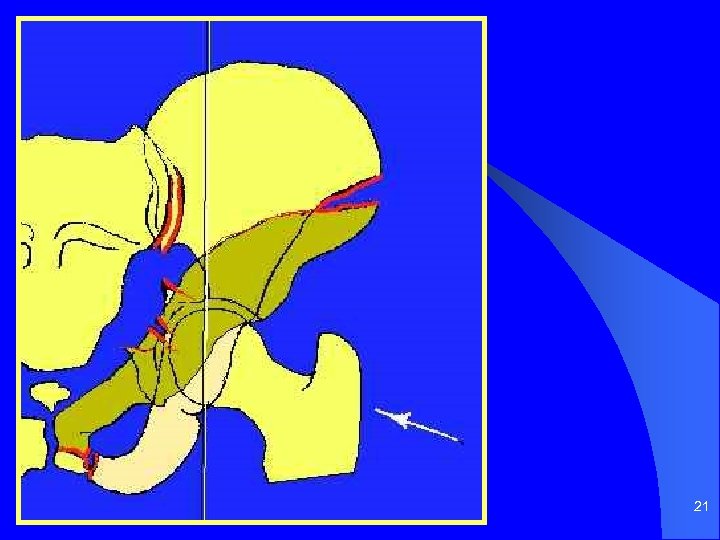

20

21